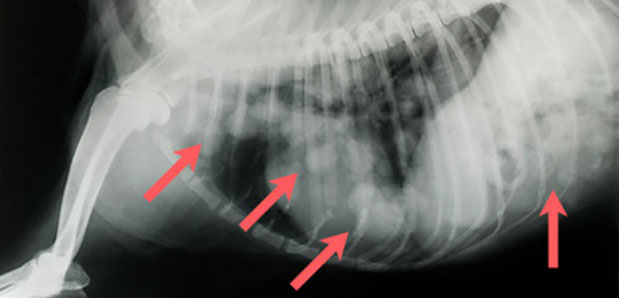

Knochenkot im Magen und Darm eines Hundes nach Grillparty